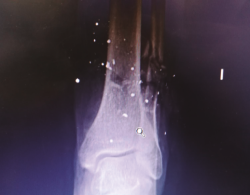

Figura 2. Radiografía tomada en urgencias. Se aprecia fractura del tercio distal del peroné con conminución ósea.

La fractura del peroné se trató de forma conservadora (Figura 4).

Figura 4. Radiografía tomada 5 meses después, tras el tratamiento conservador.